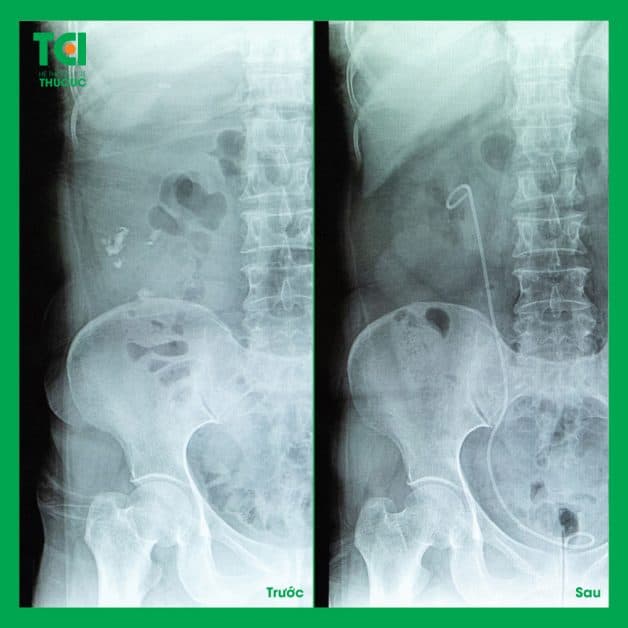

Kết quả sau khi thực hiện loại bỏ sỏi bằng phương pháp điều trị sỏi tiết niệu công nghệ cao của bệnh nhân tại TCI